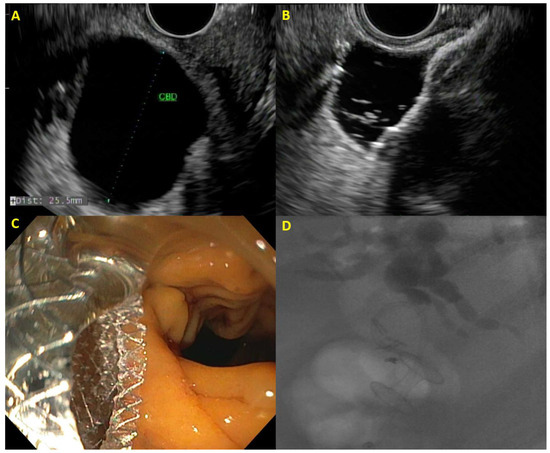

Gastric outlet obstruction (GOO) can occur in up to 20% of patients with PDAC, compromising nutritional status and quality of life in these patients [38]. Treatment has typically entailed the placement of a duodenal SEMS or surgical gastroenterostomy. Analogous to EUS-CD, the development of the EUS-guided gastroenterostomy (EUS-GE) has been greatly simplified with the development of LAMS. The jejunum distal to the site of obstruction is typically irrigated with a mixture of saline, contrast, and methylene blue and under EUS visualization, a loop of jejunum is punctured with the LAMS catheter with deployment of the distal flange of the stent in the jejunum and proximal flange of the stent in the gastric lumen (Figure 3). In this manner, EUS-GE bypasses the site of the obstruction completely, eliminating the risk of tumor invasion into the stent as seen with duodenal stents.

Figure 3. Example of EUS-guided gastroenterostomy with (A) malignant duodenal obstruction, (B) jejunum identified on EUS, (C) distal flange of lumen-apposing metal stent deployed within the jejunum, and (D) proximal flange of gastrojejunostomy stent deployed in stomach with jejunum visible through stent.